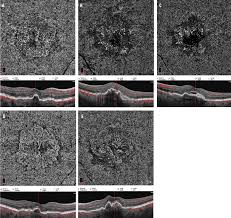

Evaluation Of Microvascular Changes In The Perifoveal Vascular Network Using Optical Coherence Tomography Angiography Octa In Type I Diabetes Mellitus A Large Scale Prospective Trial Bmc Medical Imaging Full Text

The Impact Of Macular Edema On Microvascular And Metabolic Alterations In Retinitis Pigmentosa Springerlink